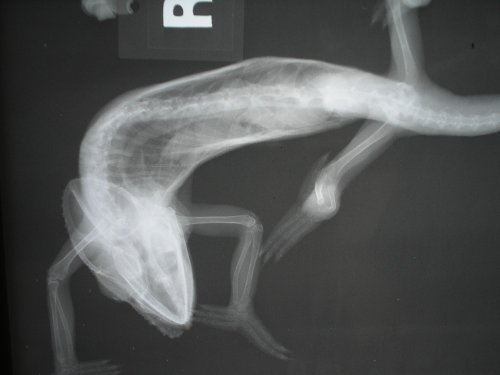

Well I made it to the vet yesterday and took some pictures of the xrays. Conditions weren't all that great and my camera was not cooperating, this is the best I got of the three xrays that were done intially.

head.JPG

whole body top.JPG

whole body side.JPG

The film for the last one was extremely dark and you can see the reflection in the photos, that is the best I was able to get.

While in the process of removing the skin I felt something that made me cringe. Anyone that have ever had a broken bone know what I am taking about. The feeling of bone sliding on bone. It was on his right side, basically where the first ribs that connect to their "sternum", dunno if its the same for them. I palpated a little more and felt it again, I also noticed considerable deflection of the area when compared to the other side. So I head to the vet with a pretty good idea of where and what to look for in the xrays, but as you just saw the angles were not very good for viewing that area.

A few more were taken however we were not able to get a clear enough picture of that area to make a definitive diagnosis. Pictures were taken of all of them xrays, 7 views in total, and sent out to another expert. I was supposed to get the same email with the photos but there must have been an issue with the mail servers. When I do get the pics Ill post them as well.